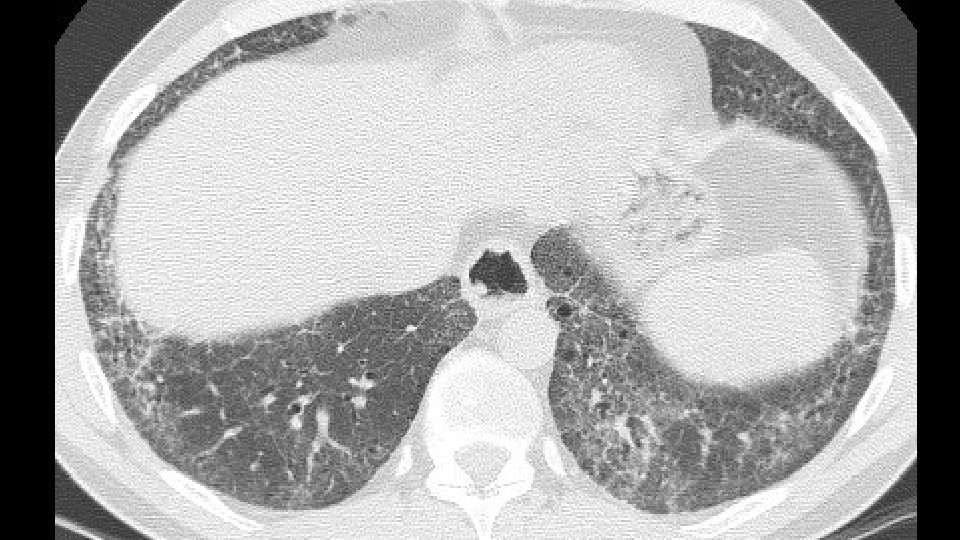

ADDITIONAL HISTORY Patient underwent five cycles of cyclophosphamide (750 mg/mq) EKG and LAB tests: Normal/negative Dyspnea persisted CT scan was repeated seven months later followed by a VATS B

Increase of cysts in the contest of reticulation a ground glass attenuation

Progressive decrease of subpleural sparing

VATS Bx: Fibrosis with honeycombing, in some areas patchy